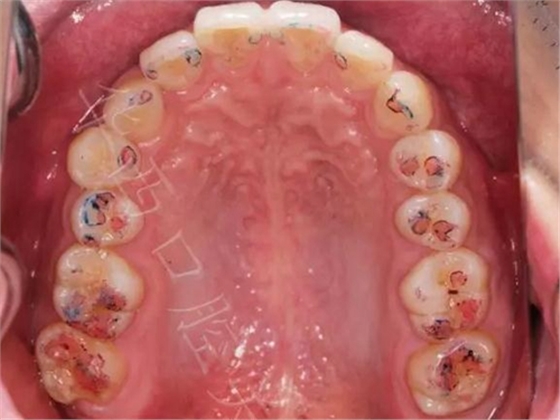

02,功能運動咬合點

①咬住200微米藍色咬合紙,前后左右磨,

▲ 圖5:200μm咬合紙

▲圖6:200µm 功能運動